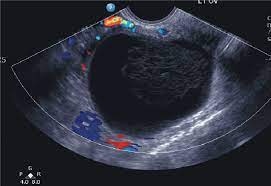

While ovarian cancer has the lowest survival rate for all cancers, 92 per cent of patients will. Type of ovarian cyst that can turn into cancer it's the dermoid cyst, also called a teratoma or mature cystic teratoma (mct). He doesn't think my reflux problem is related to my pelvic pain. Ovarian cysts of less than 1 centimeter (0.4 inches) in size are common in postmenopausal women, the vast majority of which will be benign. These benign cysts originate from germ or embryonic cells and thus contain different kinds of tissue such as cartilage, bone and skin.

A general gynecologist can remove a cyst. Ovarian cysts are common among women of all ages. They occur mostly in young women and are even found in children. This is a common phenomenon in late postmenopausal women, which can trigger swelling of the ovaries along with the formation of ovarian cysts. Staying educated about ovarian cysts is important for all women to understand their bodies and know what is and isn't normal. In the literature, its prevalence varies from 2 per thousand to 2%. Can 19mm ovarian dermoid cyst be mistaken (misdiagnosed) with any another cysts? Unfortunately he was right and i was stage iiibe. Hi, i am new to the forum and chat. Ovarian cysts of less than 1 centimeter (0.4 inches) in size are common in postmenopausal women, the vast majority of which will be benign. The ratio of cancers caused by dermoid cyst among malignant germ cell ovarian tumors is 2.9% (1, 2). The cancer surgeon can remove the mass, and if it is determined to be cancer, can also remove lymph nodes to see if the cancer has spread. Can ovarian cancer be mistaken for functional cysts?

Ovarian cancer and cysts have similar symptoms and signs, for example, pain during intercourse, pelvic pain, and urinary problems. After pleading with one doctor to finally listen to her, she got a much more. Mature cystic teratomas, also called dermoid cysts, rarely undergo a malignant transformation, i.e. Yesturday i had keyhole surgery to remove what they thought was just a normal 6cm cyst on my right ovary. Ovarian cancer starts in the cells lining the ovaries. Every year, 7,000 women are diagnosed with ovarian cancer and 4,300 women lose their lives to it. Malignant ovarian cysts are only seen in rare cases, with the benign being the most common of them all. These benign cysts originate from germ or embryonic cells and thus contain different kinds of tissue such as cartilage, bone and skin. However, as women, this is something we need to be talking about. What is dermoid ovarian cyst? The largest type of ovarian cyst is called a cystadenoma. Her surgery was due to multiple painful complex cysts on her uterus. This is one of the main reasons why ovarian cancer is so difficult to detect at an early stage.